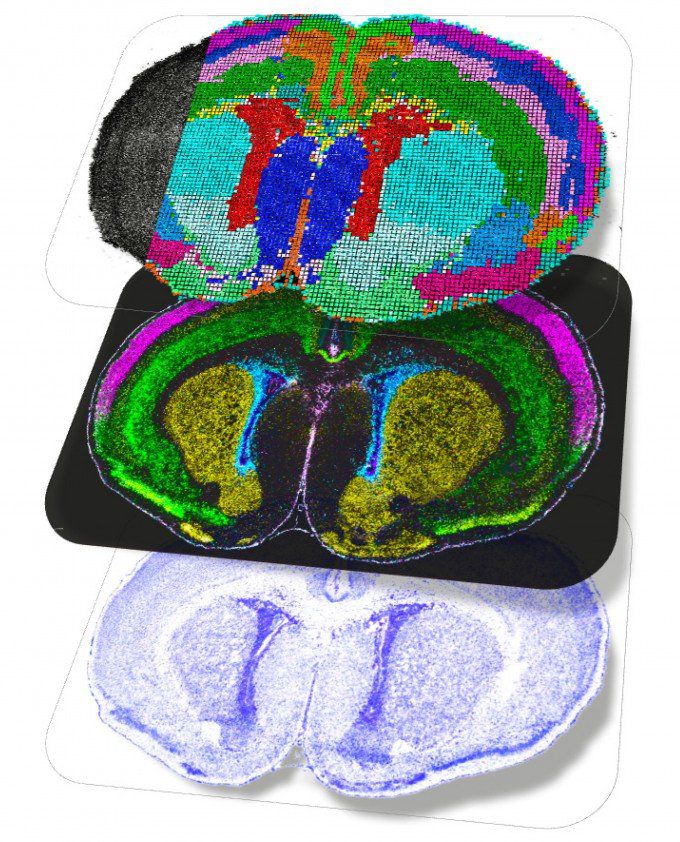

출생 직후 쥐의 뇌 공간 지도. 단백질이나 리보핵산(RNA) 등이 실제로 뇌의 어느 위치에서 상호작용하는지를 보여준다. 네이처 제공 |

과학자들이 인간과 쥐를 포함한 포유류의 뇌 발달 과정에서 다양한 뇌세포 유형이 어떻게 분화되는지 추적하는 지도를 처음으로 구축했다. 포유류의 뇌세포는 출생 후에도 발달 과정을 이어 갔다. 청소년기까지 새로운 세포 유형이 지속적으로 형성된다는 사실도 확인됐다. 이미 성숙한 성인의 뇌에서는 파악하기 어려운 일부 신경발달장애나 정신질환의 근원을 알아낼 기반이 될 것으로 기대된다.

인간의 뇌가 발달하는 과정에서 형성되는 세포 유형은 수천 종에 달한다. 세포들은 급속히 변화하기 때문에 과학자들은 정확한 뇌세포 분화 과정을 이해하는 데 어려움을 겪는다. BICAN 연구진은 고해상도 이미지 처리 기술과 첨단 계산 도구 등을 활용해 뇌 발달 과정에서 뇌세포 유형이 어떻게 출현하고 다양화·조직화되는지 추적했다.

앨런연구소 연구팀은 쥐의 뇌 발달 초기부터 청년기까지 77만 개 이상의 개별 세포를 추적해 대뇌 시각 피질 내 모든 세포 유형의 발달 과정을 기록했다. 그 결과 기존 예측과 달리 뇌세포가 출생 후에도 발달을 활발히 이어간다는 사실이 발견됐다. 눈을 처음 뜨는 순간이나 뇌가 시각 정보 처리를 배우기 시작하는 순간과 같은 중요한 시점을 중심으로 청소년기까지 새로운 세포 유형이 지속적으로 형성된다는 것이다. 출생 후 겪는 경험이 뇌의 신경회로 구축에 영향을 미치는 비중이 기존 예상보다 크다는 의미로, 출생 이후 발달장애 치료 가능성을 확인한 것으로 평가된다.